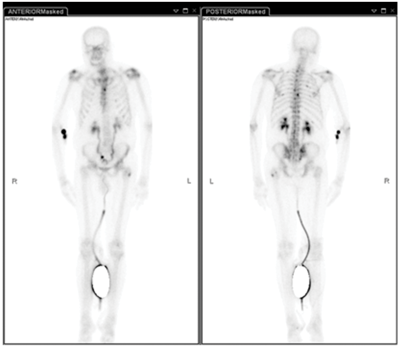

Case 3

-

Radionuclide bone scan.

Technetium 99m, Gamma camera.

6.5mSv.

2-4 hours